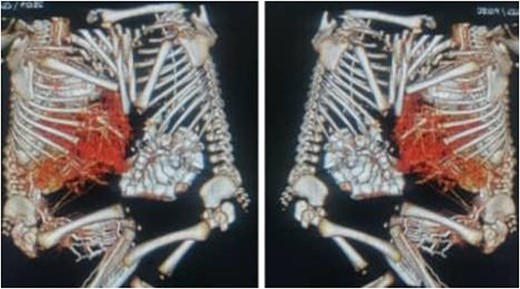

Following the placement of central lines, the two babies were anathesized and stabilized with vital sign monitoring and fluid adjustments. Then, using monopolar and bipolar diathermy, incisions and flaps were made until the peritoneum, where complete fusion of the liver with a sinusoidal connection was discovered. The connected surface area is ⁓8 by 6 cm, primarily in the caudal lobe, whereas twins B has one lobe liver and one gall bladder (Fig. 4). The xiphoid process, sternum, pleura and pericardium were all visible in the patient and were successfully separated. To avoid the occurrence of compartment syndrome, the abdomen was left as a shallow cavity with only skin closed as a neonatal hernia, then hemostasis was secured via PDS sutures and drains were placed, admitted to neonatal intensive care unit and received blood and fresh frozen plasma. The patients recovered well from anesthesia on the second day, were taken off mechanical ventilation with normal vital signs, and began Nasogastric tube tube feeding 48 h later. Patients began to gain weight and were discharged the next day to be seen at a referral clinic.